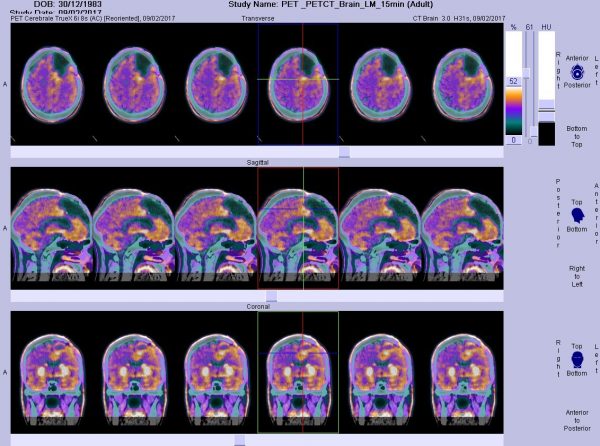

Imaging Tests

The imaging tests can offer comprehensive details about the structure of the brain and its abnormalities. Using sophisticated imaging tests, it is possible to get a clear picture of the brain and locate the tumor. The following imaging tests help the doctor detect the presence of a tumor in your brain:

- PET (Positron Emission Tomography)